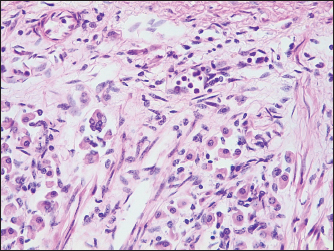

In the endocardium, as well as in the associated myocardium, multiple severe hemorrhages were observed. The blood vessels of the lungs were dilated and filled with erythrocytes. In some areas, there was thickening of the interstitium, with mild to moderate numbers of lymphocytes, while the BALT was slightly hyperplastic. In some sectors, edema was observed in both alveoli and bronchioles, with the presence of some areas of atelectasis. In the stomach, a moderate dilatation of the submucosal lymphatic vessels was observed, with the presence of a multifocal inflammatory infiltrate composed of lymphocytes, plasmacytes, and some neutrophils (Fig. 2). In the gastric lumen, basophilic structures of approximately 2,1-3 µm in individual diameter forming bundles were observed, with morphology suggestive of Sarcina spp. The size was obtained using Image J software by measuring 20 individual bacteria. In the small intestine, the villi were slightly atrophied. In the mucosa, some parasitic structures compatible with Strongyloides spp. were observed. In one sector, on the intestinal surface, basophilic structures forming bundles compatible with Sarcina spp. were observed (Figs. 3 and 4). The lamina propria as well as the submucosa showed edema with an inflammatory infiltrate with a moderate amount of lymphocytes and plasmacytes, and to lesser extent neutrophils, macrophages, and eosinophils, as well as a marked hyperplasia of the lymphoid tissue. Finally, a moderate to severe eosinophilic and lymphocytic infiltrate was observed in the lamina propria of the large intestine. The lymphoid tissue of the submucosa showed severe hyperplasia, with a large number of apoptotic bodies. In one sector, on the surface of the organ, basophilic structures forming bundles were observed, compatible with Sarcina spp. When Gram staining was performed, these microorganisms were observed as Gram-positive bacteria (Fig. 5). In the liver, there were some small inflammatory foci composed of a few neutrophils and some lymphocytes and macrophages. No alterations in the nervous plexuses of the gastrointestinal tract or other relevant histological alterations were observed in the rest of the organs examined. Finally, it was concluded that the death was produced as a consequence of a multiorganic failure associated with a severe tympanism of the digestive tract.

Fig. 2. Stomach: mild inflammation in the lamina propria with presence of neutrophils, lymphocytes, and plasmacytes (H&E, 400×).